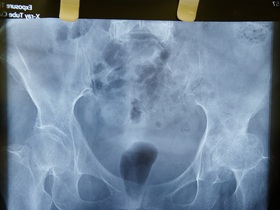

Показання до КТ-діагностики

Зробити КТ у Києві в нашому консультативно-діагностичному центрі варто, якщо у вас спостерігаються такі клінічні симптоми та стани, як:

- тяжкі травми (голови, хребта, а також поєднані ушкодження);

- головний біль, непритомність, порушення зору, причина яких не була виявлена іншими методами діагностики;

- патологічні процеси у внутрішніх органах, включаючи онкологію (для уточнення діагнозу, а також контролю за динамікою патології);

- захворювання хребта з болем зосередженим в ділянці шиї, спини, кінцівок (особливо, якщо в клінічній картині спостерігаються порушення рухливості, оніміння та поколювання кінцівок).